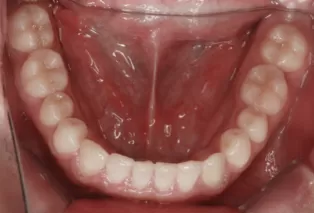

Intraoral photos after treatment